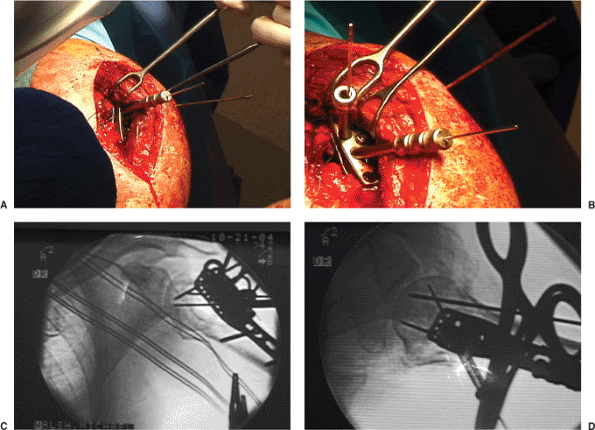

plate with angular stable screws is utilized (Locking Proximal Humeral

Plate, Synthes USA, Westchester, PA) (Fig. 3.12). The plate is applied to the proximal lateral humerus just lateral to the biceps tendon and

held with 1 or 2 K wires. The height of the plate is evaluated with the

image intensifier to insure that the plate is not prominent superiorly (Fig. 3.13).

A standard cortical screw is placed in the oval hole in the plate,

lightly tightened and adjusted (as judged through fluoroscopy). To

insert the locking screws into the head, a triple drill guide is

threaded into the plate. A locking drill sleeve is threaded into the

plate, and based on image intensification in two planes, a guide wire

is advanced into the reduced humeral head (Fig. 3.14).

Figure 3.14. A. Intraoperative photo of the plate and the first provisional guide pins inserted into the humeral head. B. Intraoperative photo of the plate and 2 guide pins. C. Fluoroscopic AP and D. axillary lateral images documenting the correct position of the guide wires within the humeral head.

|